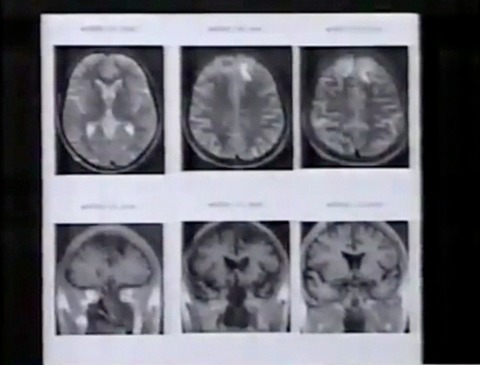

脳の状態に問題はないのか。MRIという画像診断装置を使って、詳しい検査を受けます。

その結果、脳に異常が発見されました。

前頭葉と呼ばれる、脳の前の部分に白い塊があります。神経細胞が死滅したあとです。前頭葉は、計算や思考など、創造的な働きを担う中枢です。ウラジミルさんの知的障害の原因は、ここにあるのではないかと医師たちは考えています。

脳の更に深い部分にも、神経細胞が死滅したあとがありました。ウラジミルさんの疲労感や脱力感の原因は、これではないかと診断されました。